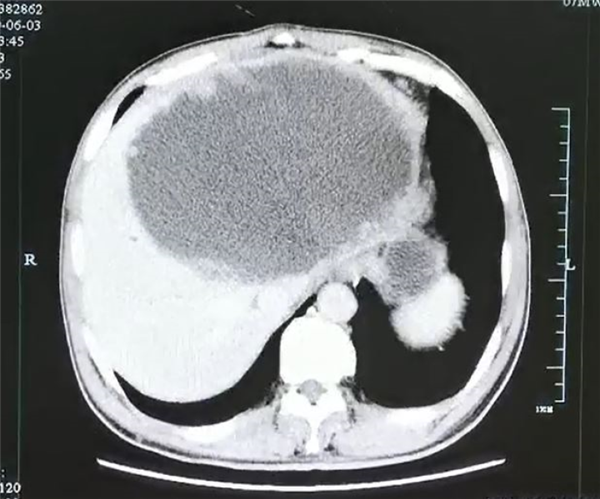

杭州的谢师傅由于进食了未完全加热成熟的酸菜鱼而感染了“华支睾吸虫”,导致左肝几乎已经被“掏空”了,变成了一个大脓球。

病理显示,脓肿壁上大量的肿瘤样结构,是肉芽肿性炎性肿块,里面爬满了灯泡状、壳厚的华支睾吸虫虫卵。